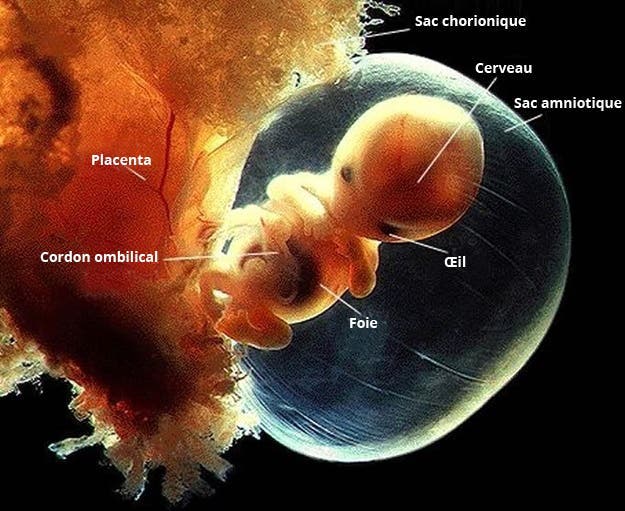

4 – À environ 10 semaines de grossesse

Tous les organes majeurs du corps sont opérationnels : les reins, les intestins, le cerveau et le foie sont tous fonctionnels. Ses bras et ses jambes commencent aussi à se courber pour prendre leur forme naturelle.